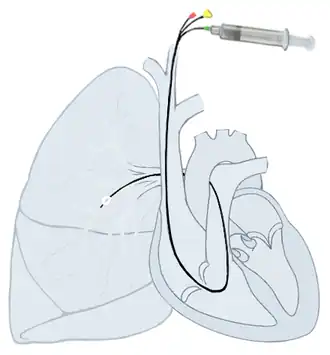

Right heart catheterization (RHC)

Right heart catheterization (RHC) allows the physician to determine the pressures within the heart (intracardiac pressures). The heart is most often accessed via the internal jugular or femoral vein; arteries are not used. Values are commonly obtained for the right atrium, right ventricle, pulmonary artery, and pulmonary capillary "wedge" pressures. Right heart catheterizations also allow the physician to estimate the cardiac output, the amount of blood that flows from the heart each minute, and the cardiac index, a hemodynamic parameter that relates the cardiac output to a patient's body size. Determination of cardiac output can be done by releasing a small amount of saline solution (either chilled or at room temperature) in one area of the heart and measuring the change in blood temperature over time in another area of the heart.

Right heart catheterization is often done for pulmonary hypertension, heart failure, and cardiogenic shock. The pulmonary artery catheter can be placed, used, and removed, or it can be placed and left in place for continuous monitoring. The latter can be done an intensive care unit (ICU) to permit frequent measurement of the hemodynamic parameters in response to interventions.

Parameters obtainable from a right heart catheterization:

- Right atrial pressure

- Right ventricular pressure

- Pulmonary artery pressure

- Pulmonary capillary wedge pressure

- Systemic vascular resistance

- Pulmonary vascular resistance

- Cardiac output

- Blood oxygenation